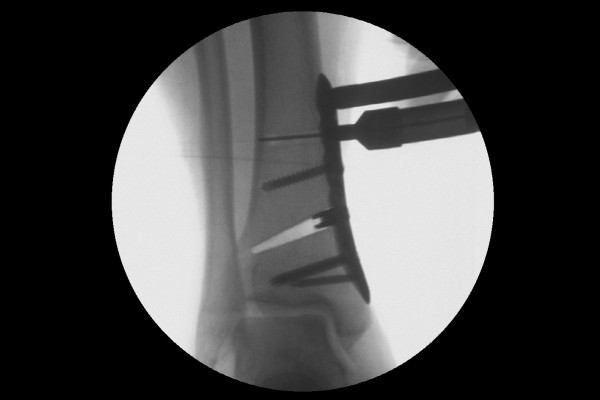

실시간 X-RAY인 C-ARM을 이용하여 확인하며, 안쪽 뼈에 실금을 내어 벌리고서 금속판을 이용하여 고정합니다.